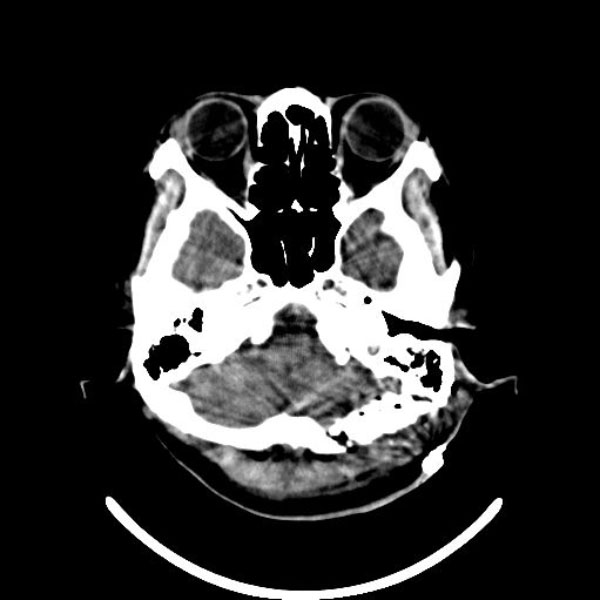

手術前

(MR1)

手術後

(CT)